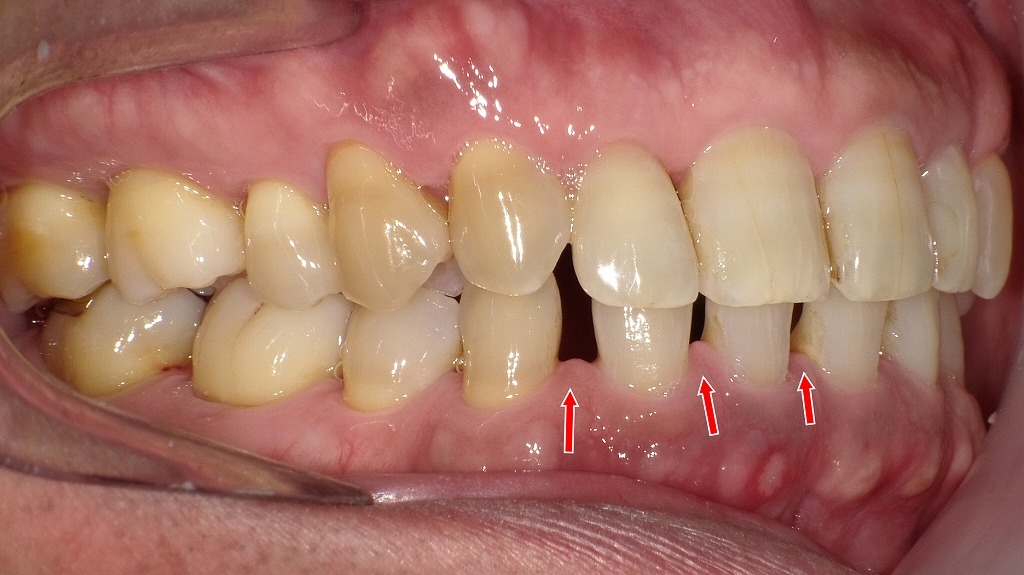

【右側面観と左側面観】

◆ 全体として考えられる影響

- 小臼歯欠損により前歯がすきっ歯のまま安定しやすい

- 噛み合わせのバランスが悪く、長期的には咬耗・歯肉退縮・歯周病リスクも上昇

- 空隙部に食片が入りやすく、清掃性が低下しやすい

- 審美的な問題(前歯の隙間)が日常生活に影響する可能性